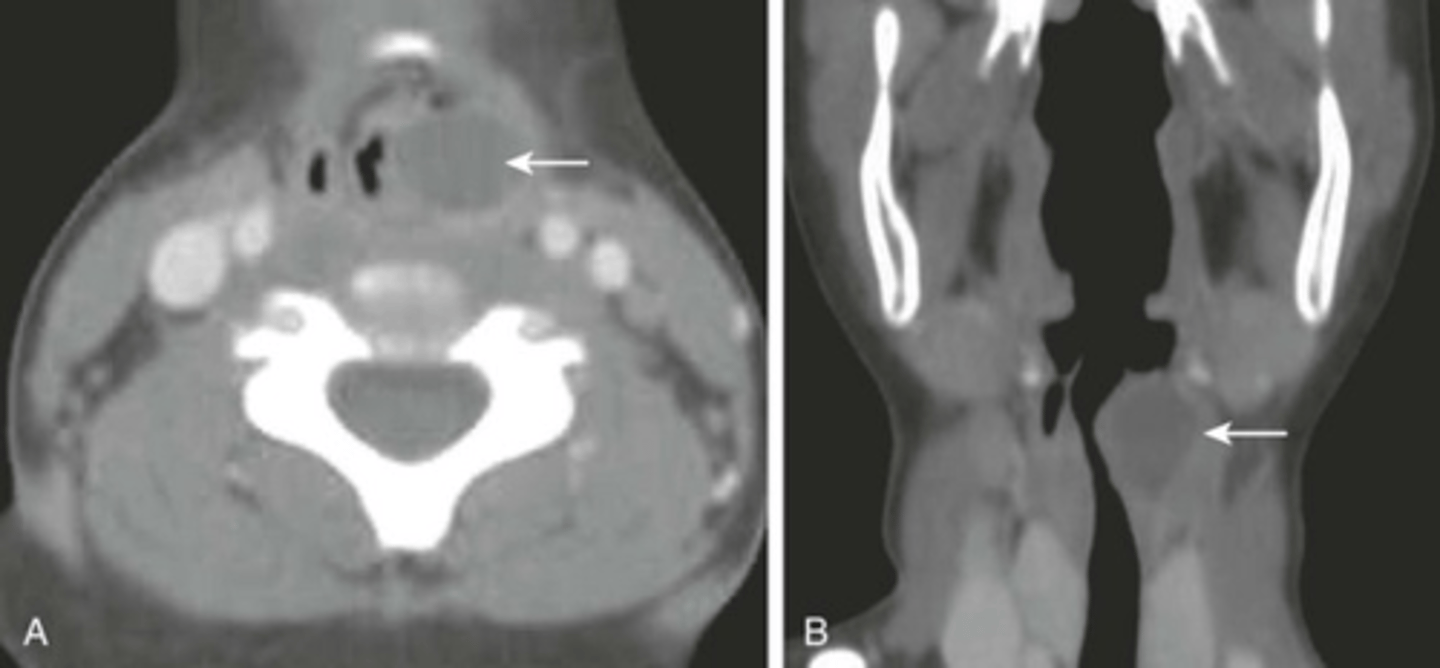

Thyroid Cancer

Abnormal cells multiply in the thyroid, forming a tumor.

Where is the thyroid gland located?

Inside the lower anterior portion of the neck. around the level of cricoid cartilage

Is thyroid cancer treatable?

Yes, when caught early it is one of the most treatable forms of cancer

Why does a thyroid mass appear nonsymmetrical?

Because the thyroid gland is bilobed.